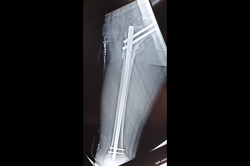

Tibia Nailing